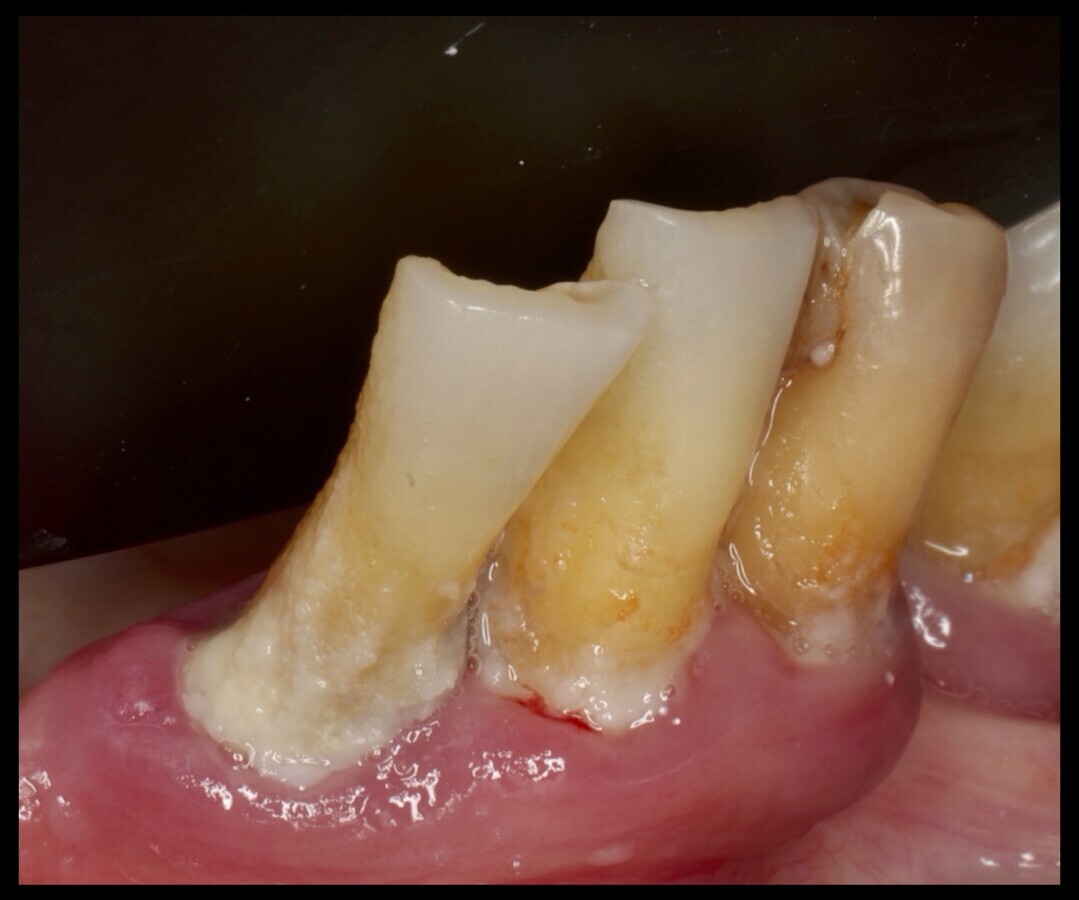

Paciente medicado con múltiples fármacos que padece xerostomía.

La hiposalivación o reducción de la tasa de flujo salival inducida por medicamentos aumenta el riesgo de varias enfermedades bucales, incluyendo caries dentales, especialmente en lugares atípicos (alto riesgo de caries radiculares e incisales), mayor riesgo de candidiasis, mal aliento, ardor en la boca, trastornos del gusto y dificultades en la masticación, habla y deglución[2].